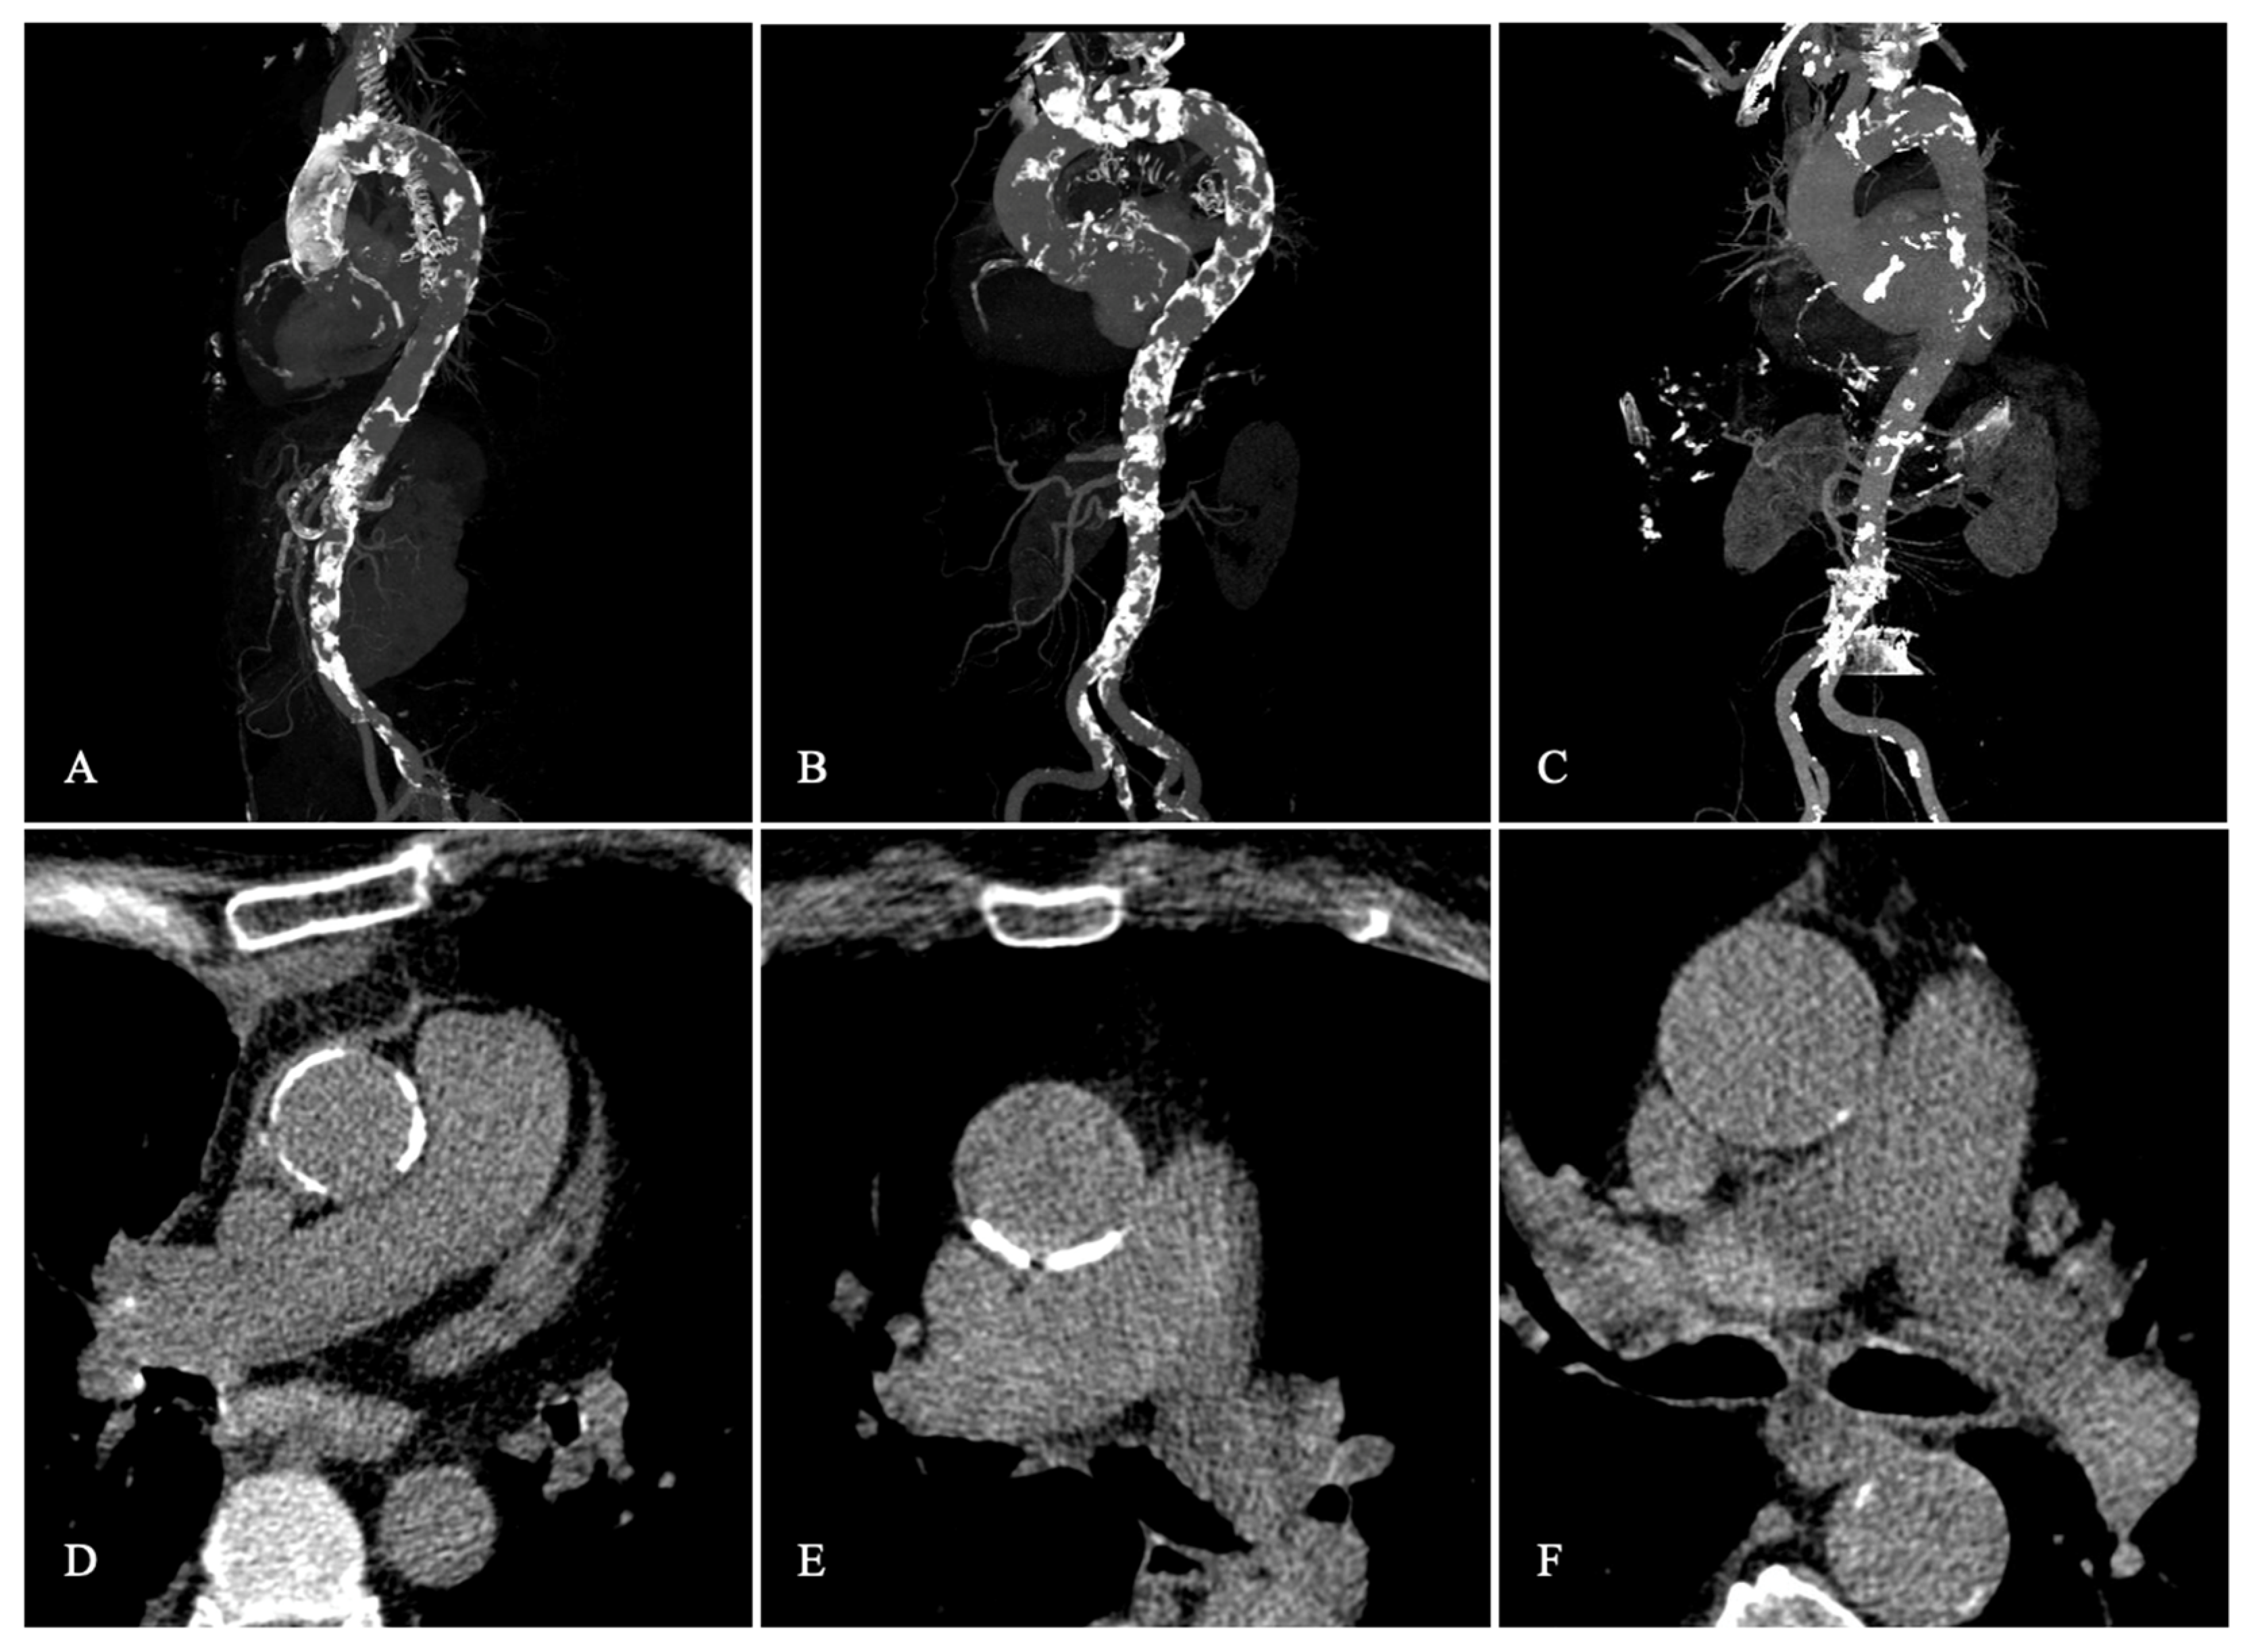

2.3. Definition of Porcelain Aorta